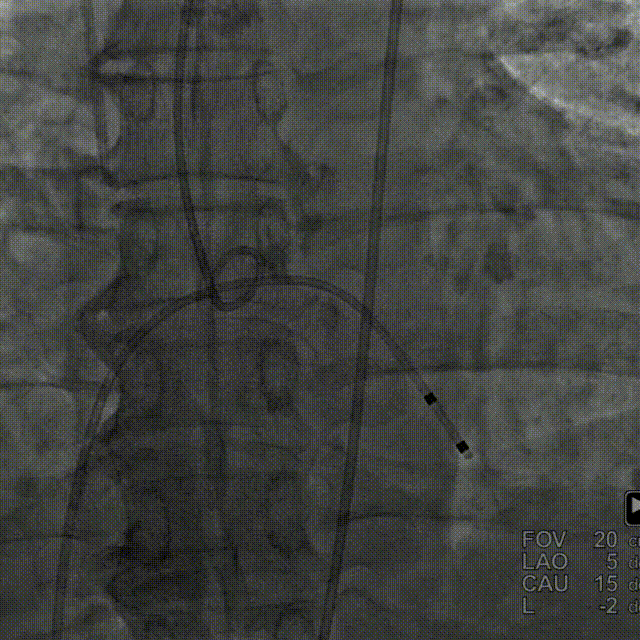

• 术中使用跨瓣角度为LAO 5° CAU 15°(右窦中心位),22mm球囊预扩张,球囊预扩角度为LAO 16° CAU 2°(左冠切线位);

主动脉根部造影,主动脉狭窄伴有明显反流,采用22mm球囊预扩,轻微腰征,造影无漏。

主动脉根部造影

球囊预扩